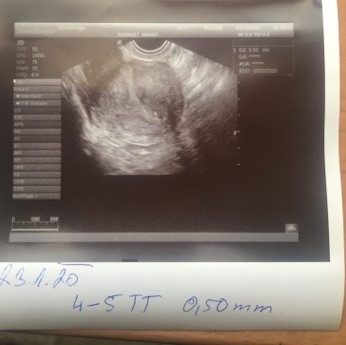

@agamacka ahojky já byla ve čtvrtek na těhu kontrole váček měl 0,50cm tj těch 5mm a říkala mi dr,že je to tak 4-5tt a to jsem dnes 4+4tt 😀 😀 a dálnice na testu se mi ukázaly teprve dnes,jinak jsem měla slabé čárky 🙂 🙂

@agamacka no to určo budeš tak 4-5tt,já tak byla a měla jsem úplně stejnou velikost 🙂 🙂